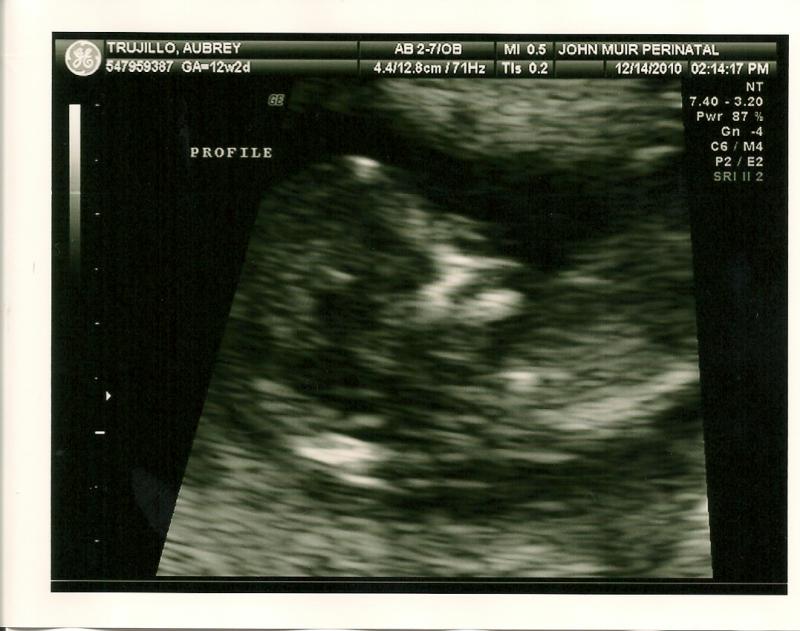

We got to see our little one's heartbeat that day!  This is all starting to feel so real....12 weeks, 2 days

We heard the heartbeat that day! 164 bpm!!!